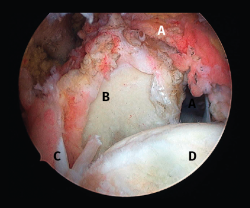

Figura 3. Rotura del manguito rotador en forma de L. A: tendón infraespinoso; B: tendón supraespinoso; C: glena; D: cabeza humeral.

Figura 5. Rotura de tipo C1. A: rotura pequeña de espesor completo del supraespinoso; B: cabeza humeral.

Sin embargo, las clasificaciones basadas en el tamaño de la rotura deben ser bidimensionales, ya que la visión unidimensional puede ser engañosa, al mostrar el tamaño de la rotura solo desde el plano anteroposterior(4). Por esta razón, proponemos el sistema de clasificación del manguito posterosuperior sugerida por Snyder, que aporta información no solo del tamaño, sino del número de tendones afectados y la presencia de tejido cicatricial(7). En las lesiones de tipo C1 la lesión atraviesa todo el espesor del tendón y en el eje transversal es pequeña y punzante (Figura 5). Las de tipo C2 son roturas de espesor completo pero la distancia entre los extremos de la rotura es menor de 2 cm con escasa retracción (Figura 6). En las de tipo C3 la rotura afecta en sentido transversal entre 3 y 4 cm con mayor retracción implicando 2 tendones (Figura 7). Y las de tipo C4 son la rotura masiva del manguito de los rotadores con una afectación de espesor completo de toda la anchura de 2 o más tendones asociando importante retracción (Figura 8).

Figura 8. Rotura de tipo C4. A: rotura masiva del tendón supraespinoso con presencia de degeneración grasa; B: glena; C: rotura masiva del tendón infraespinoso; D: cabeza humeral.